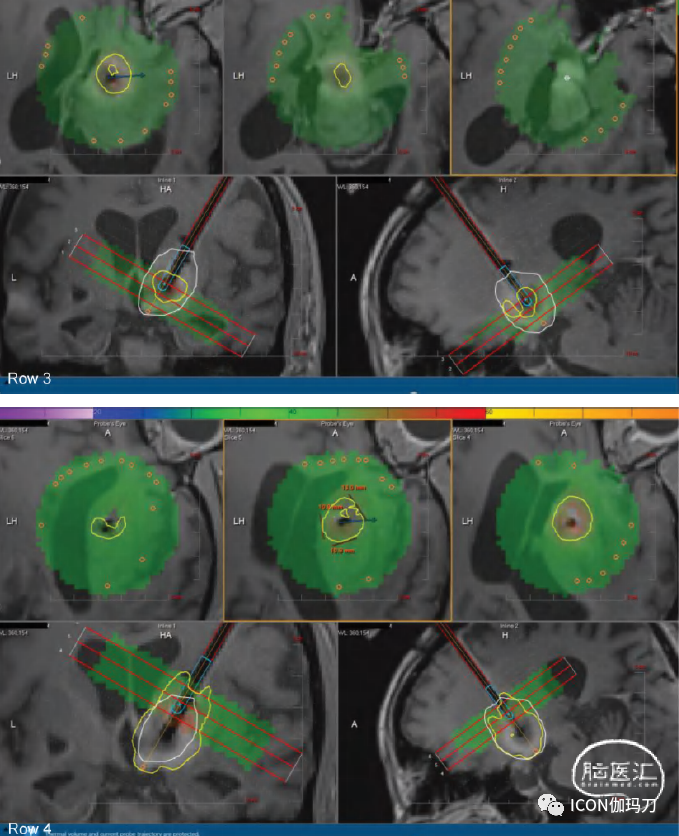

36.5.3 激光热凝固术

对于不太容易外科手术接近的病变,一种更近期的外科技术称为激光热凝固术(laser thermocoagulation)或激光间质热治疗(laser interstitial thermotherapy,LITT)已经发展起来,以满足组织诊断和治疗放射性坏死的需要。自十年前推出以来,它被越来越多地使用,包括在标准开颅手术可治疗病变的患者中。这部分是因为该技术的微创性,尽管在大多数中心,这些患者仍然需要全身麻醉。在此过程中,在头皮上做一个小的刺入切口和在颅骨上做一个5毫米的钻孔,以帮助病变活检首先提供诊断。然后,沿着相同的轨迹,病变可以使用二极管激光进入病变中心进行消融。激光发出的光在周围的组织中转化为热。然后使用连续术中MR梯度回波成像监测热传递的进程。然后使用专有软件计算实时消融图,利用每个成像体素处于升高温度的时间,使外科医生能够监测并确定消融何时完成(图36.5)。术后患者通常需要在夜间观察,由于切口小且没有开颅手术,很少需要疼痛管理。大多数患者可以在术后第一天回家。

图36.5(第1排)肺癌患者在接受18 Gy的 SRS治疗后1年维持TKI,且右侧基底神经节病变再次生长。(第2行)在LITT手术开始时,激光纤维被立体定向地放置在肿瘤中间(白色轮廓)。上面3排是消融图,黄色圆圈显示从激光光纤周围开始热扩散的位置。(第三排)手术后期,黄色圆圈表示热通过病灶扩散。(第4行和第5行)LITT治疗消融完成时在治疗软件窗口和标准解剖平面估计区域的黄色轮廓包围肿瘤。(第6行)LITT后2周T1加权钆剂增强和 MRI的FLAIR序列显示强化病灶大小稳定,脑水肿早期减少。(第7行)LITT治疗后6周,病灶尺寸减小,周围脑水肿减少。

与开颅手术相似,多项回顾性研究显示,LITT对治疗SRS治疗后病灶再生长有效,无论病理是放射性坏死、肿瘤再生长,还是两者结合。

由于LITT提供微创开颅手术的选择,根据我们的经验,当提供这种选择时,更多的患者愿意考虑接受手术治疗。最大的前瞻性、多中心的LITT(立体定向放射外科治疗后激光消融)研究观察了使用LITT治疗SRS治疗过的病灶再生长的长期结果。研究招募到42名患者。他们的6个月总体无进展生存率为75%,3个月总体生存率为86.5%,6个月总体生存率为72.2%。30%的患者能够在术后3个月停止或减少类固醇的使用。经病理分析,经活检证实肿瘤再次生长的患者6个月时局部控制率为74%,而经活检证实的放射性坏死患者6个月时局部控制率为100%。中位住院时间为肿瘤患者2.3天,放射性坏死(RN)患者1.7天。亚分析进一步表明,虽然总体消融术和次全消融术可以很好地控制放射性坏死病变(病变稳定或有应答反应),但正如预期的那样,62.5%的患者在LITT后,次全消融术不足以控制肿瘤的再次生长和进一步生长。这一发现导致了在实践中改变在我院患者病程中较早提供LITT术。通常情况下,如果之前SRS治疗过的病变分别在6周或6周以上的两次连续MRI扫描中显示有持续生长,则在可行的情况下讨论LITT作为一种治疗方案。这种考虑在接受免疫治疗的患者中尤为重要,因为如前所述,这不仅增加了放射坏死的机会,而且需要避免在这一人群中使用类固醇。